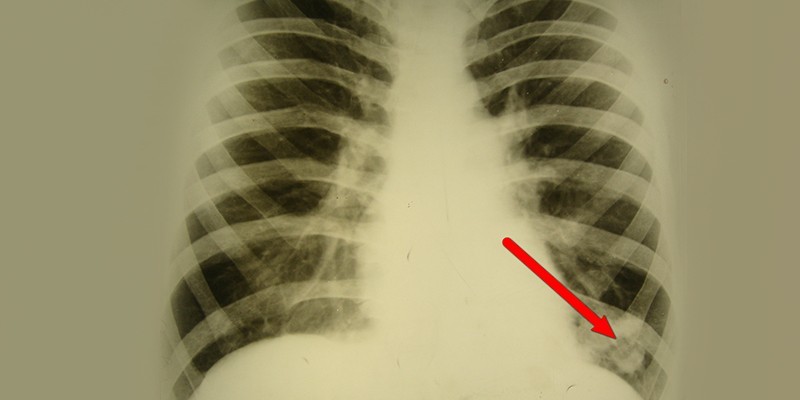

Хронический абсцесс нужно дифференцировать от туберкулеза, актиномикоза, полостной формы периферического рака легкого. Основная диагностика проводится по тем же принципам, что и при подозрении на острую форму гнойного воспаления. У большинства пациентов с хроническим абсцессом в анамнезе обнаруживается перенесенное ранее гнойно-деструктивное воспаление. Диагностика включает следующие исследования:

- рентгенологическое исследование;

- компьютерная томография легких;

Для постановки диагноза пациенту предложат сдать анализ крови и мочи, проведут анализ выделяемой мокроты и бактериоскопию с бакпосевом, что позволит точно выявить возбудителя и определить его чувствительность к медицинским препаратам. Также проводится рентгенография легких, КТ и МРТ легких и ряд других исследований.